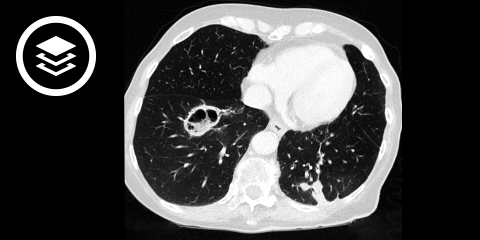

Für eine postprimäre Tuberkulose sprechen Oberlappen-betonte, heterogene, oft fleckige Konsolidierungen. Ferner findet man unscharf begrenzte, lineare oder noduläre Verdichtungen. Im Vergleich zur Primärtuberkulose treten deutlich häufiger Kavitäten bzw. Kavernen auf, sie kommen in 20 bis 45 % der Fälle vor. Weitere radiologische Merkmmale sind Bronchialwandverdickungen und als Zeichen der aktiven endobronchialen Dissemination zentrilobuläre und azinäre Lungenrundherde mit Tree-in-Bud-Muster sowie lobuläre Konsolidierungen.

Bei der Miliartuberkulose zeigen sich scharf begrenzte Mikronoduli mit zufälliger (miliarer) Verteilung.

CT-Fallbeispiel

DICOM-Modelle können auf Mobilgeräten leider nicht angezeigt werden.